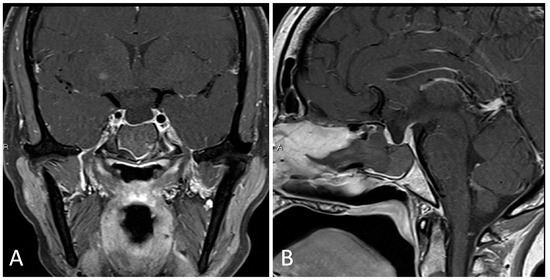

3.4.2. Illustrative Case